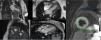

Coronary computed tomography angiography (CCTA) revealed a single coronary artery with its ostium in the right sinus of Valsalva (RSV), agenesis of the left main artery and a hypoplastic LAD, the RCA with a normal course, antegrade flow through a posterior lateral branch (PLB) to the LCx and LAD, and collaterals originating from the posterior descending artery (PDA) to the distal segment of the LAD. All coronary arteries were patent and with no evidence of atherosclerotic plaque (Figure 4).

Coronary computed tomography angiography depicting a single coronary artery with its ostium in the right sinus of Valsalva (arrow), agenesis of left main artery and hypoplastic left anterior descending artery; right coronary artery with a normal course. All coronary arteries were patent with no evidence of atherosclerotic plaque.

Cardiac magnetic resonance imaging (MRI), performed six days after admission, showed mild hypokinesia of the mid segments of both anterior and anteroseptal walls, preserved global LV systolic function, and diffuse myocardial edema (Figure 5), with no significant late enhancement and no perfusion defects (Figure 6), which was a clue to the diagnosis of Takotsubo cardiomyopathy.